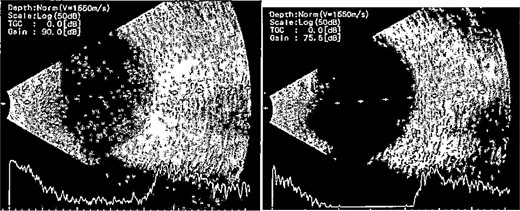

Patient 2: A 69-year-old Saudi female experienced severe right eye pain after surgery on the same day as patient 1. Visual acuity was reduced to hand motions, and examination showed conjunctival ciliary injection, corneal edema, and hypopyon (Fig. 3). B-scan confirmed vitritis (Fig. 4). She received similar emergency interventions as patient 1.

B-scan ultrasound showing moderate vitreous echoes and vitreous abscess in patient 2.